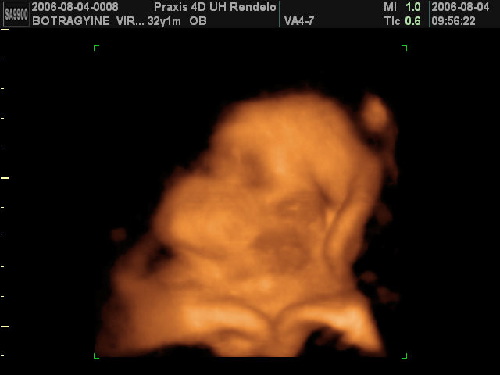

Képek szuperek!!! Irígy vagyok ám, csak nem látod milyen sárga lettem.

Képek pedig tüneményesek!

Flórácskám meg még ki sem bújt a pocakból, de már másodszor szerepel a tv-ben.